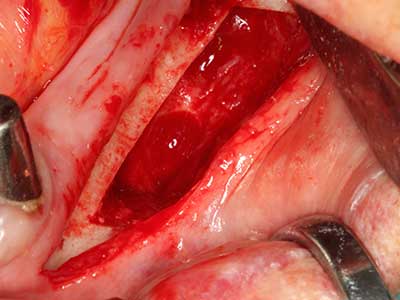

Piezosurgery has additional advantages when harvesting bone blocks. In addition to the high precision with osteotomy described above, the use of the thin saw tips specifically minimizes loss of material. Greater loss of material during harvesting can be expected with the thicker instrument tips, particularly when using Lindemann drills (Lakshmiganthan, Gokulanathan et al. 2012). The basal separation, which is necessary particularly for retromolar block transplants, is simplified by specially designed rectangular saws, with the result that piezosurgery is viewed as a precise, simple and safe procedure for harvesting retromolar bone blocks (Happe 2007) (Fig. 1-12).

Fig. 1: Preparation of a bone cover with the Piezomed (W&H Salzburg, Austria).

Fig. 3: Basal separation of the block is easier with specially angled attachments.